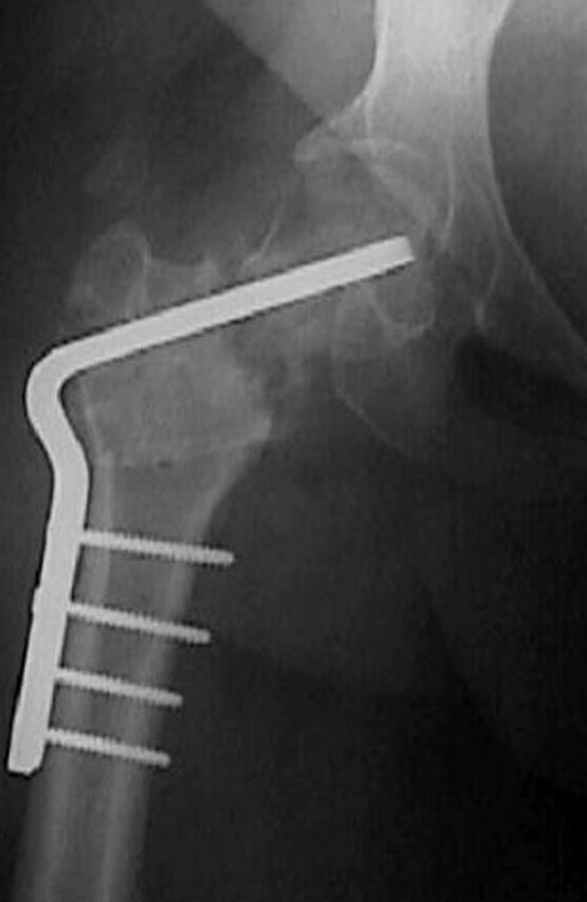

Несколько снимков из моей коллекции, чтобы разьяснить, почему мы до сих пор делаем различные варианты остеотомии.

На рисунке N1 предоперационный план лечения ложного сустава шейки бедра- линия ложного сустава, угол и направление введения импланта, клиновидная остеотомия в градусах и миллиметрах, второй снимок после коррекции, расчет, на сколько удлиняется конечность и размеры импланта;

N3 рисунок окончательный снимок, после операции моя рентгенограмма должен выглядеть примерно как эта картина. На N4 снимке клин перед удалением; N5 послеоперации 3 нед.; N6 окончательная рентгенограмма.

варус при проксимальном отделе 95 градусной пластиной.

Djoldas Kuldjanov 23 Ноябрь 2004, 18:21

пластическая модель; и коррекция бедра аппаратом Илизарова.